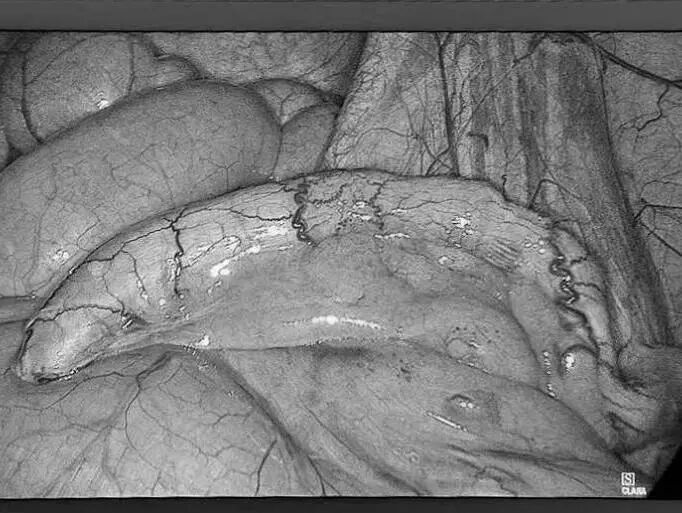

近日,贵州航天医院普外科特邀贵州医科大学附属医院胃肠外科严芝强博士前来我院开展“腹腔结核的综合治疗”学术讲座,严博士结合临床实际案例,带来了腹腔结核综合治疗的前沿知识和宝贵经验,深入浅出地讲解了腹腔结核的发病机制、诊断要点、最新治疗策略及药物精准治疗、把握手术干预时机、营养支持等关键环节,为提升我院腹腔结核诊治水平奠定了坚实基础。 今天,小编就带领大家回顾讲座内容,你想要了解“腹腔结核”知识都在这里! 什么是腹腔结核? 结核病是由结核分枝杆菌引起的传染病,曾是单一传染源死亡的主要原因,能影响身体多个器官,腹腔结核就是其中之一,包括胃肠道、腹膜、肠系膜淋巴结等部位的结核病。 腹腔结核常见症状 消化系统症状:常见为腹痛,可能伴有呕吐、腹胀、恶心、腹泻或便秘等症状。如:频繁呕吐,无法正常进食;长期受腹胀困扰,腹部隆起。 全身症状:发热、盗汗、体重减轻等。如:不明原因地体重下降,身体逐渐消瘦,夜间睡觉时大量出汗。 腹腔结核发病原因 消化道感染:食(饮)用带菌牛奶或被结核菌污染食物,进入消化道后,结核菌在肠道淋巴组织中形成病灶,并可能蔓延至肠系膜淋巴结、腹膜等部位。如,经常喝未经严格消毒的牛奶,增加感染风险。 血行播散:身体其他部位的结核菌,通过血液循环到达腹腔,侵犯腹腔内器官。如肺结核,当患者免疫力下降时,结核菌就可能“乘虚而入”进入血液,进而播散到腹腔。 淋巴结播散:胸腔内淋巴结结核或全身粟粒型结核,结核菌可通过淋巴管道传播至腹腔淋巴结,引发腹腔结核。 腹腔结核治疗方式 1.早期、联合、全程规范化抗结核治疗(治疗原则)。 2.加强支持治疗。 3.抗结核化学药物治疗:一般三联或四联。 4.放腹水,可同时腹腔内注射药物治疗。 5.手术治疗:仅限于完全性肠梗阻、肠瘘或并发肠穿孔者,当本病诊断有困难,与腹内肿瘤或某些急腹症不能鉴别时,可考虑剖腹探查。 腹腔结核饮食注意 腹腔结核患者饮食少量多餐,控制高脂、肥腻食物摄入,多吃清淡、易消化的食物,适量补充高蛋白等营养,多吃富含纤维素的新鲜蔬菜和水果,促进肠腔及腔腹部蠕动,禁食辛辣刺激性食物,忌烟酒。 腹腔结核预防建议 如果感染腹腔结核,一定要到正规医院做正规抗结核治疗,积极配合,树立战胜疾病的信心,就能战胜病魔,恢复健康。 近年来,腹腔结核发病率呈上升趋势,因其诊疗复杂、病情多变,常累及肠道、腹膜等多脏器,致患者腹痛、肠梗阻,严重影响生活质量,甚至危及生命。 对此,贵州航天医院普外科依托结核内科结核病诊疗经验,积极开展腹腔结核外科治疗工作,通过内外科联合,着力打造腹腔结核诊疗体系,为遵义地区腹腔结核患者提供更加优质、全面的诊疗服务。 咨询信息:贵州航天医院便民服务电话(请点击跳转咨询电话页面) 注:部分图片来源于网络,如有侵权,请联系删除。 贵州航天医院普外科专家团队 梁 跃 普外科主任 主任医师 临床擅长:对普外科各类肿瘤手术具有丰富的临床经验。 毕业于遵义医学院,遵义市医学会小儿外科学分会常务委员,遵义市肛肠协会理事,遵义市医学会核医学分会(第二届)委员会委员;荣获第三期“黔医人才计划”优秀学员称号;主持市级课题1项,完成省级课题1项,在国内各类刊物上发表论文10余篇。 钱科洪 普外科 副主任医师 临床擅长:从事普外科临床工作30余年,对各类普外科疾病的诊治、乳腺、甲状腺、胃十二指肠、结直肠等疾病及疑难杂症具有丰富的临床诊疗经验。 毕业于遵义医学院临床医疗系,2009年前往中山大学附属第一医院微创外科进修学习,在国内各专业期刊发表论文数篇。 贵州航天医院普外科简介 基本情况 贵州航天医院普外科成立于1968年,前身属于航天部O61基地3417医院外一科,1998年3417医院、3427医院合并后更名为普外科,下设胃肠外科、肛肠外科2个亚专业科室,拥有在全市较为先进的专科设备和技术,是中国疝病专科联盟单位,贵州医科大学附属医院胃肠外科专科联盟单位。开放床位40张,配备医护人员21人。 专科特色 普外科致力于胃肠及肛肠疾病的外科临床诊治及科研,以腹腔镜微创外科技术为本,形成以快速康复治疗胃肿瘤、结直肠肿瘤、小肠肿瘤、直肠脱垂、肥胖病、急腹症、各类疝、痔、瘘等专科特色,同时注重胃肠疾病尤其是结直肠恶性肿瘤的基础研究和临床转化研究,总体诊断和治疗水平在区域同级医院居于领先水平。 开展手术:腹腔镜下胃癌根治术,腹腔镜下袖状胃切除术,腹腔镜下胃肠道间质瘤切除术,腹腔镜下结、直肠癌根治术,胃癌、结直肠癌的精准治疗,腹腔镜下小儿疝气、成人疝修补术,腹腔镜下阑尾手术,内痔的硬化注射治疗及痔疮的微创治疗:ATH、PPH、TST,直肠脱垂的各种手术治疗,难治性伤口VSD技术,鼻胃肠管、肠梗阻导管置入术,肛肠术后间歇性导尿技术,并引进了中医适宜技术,也为各种化疗患者提供输液港安装,提高患者就医体验。 腹腔镜下腹股沟疝无张力修补术 腹腔镜下腹股沟疝 无张力修补术 腹股沟疝里金斯坦(Lichtenstein)手术 PPH微创术治疗环状混合痔 黏连性或炎性肠梗阻-肠梗阻导管 腹腔镜袖状胃切除 腹腔镜阑尾切除术 腹腔镜阑尾肿瘤切除术 腹腔镜下结肠癌根治术 诊疗范围 胃肿瘤、结直肠肿瘤、小肠肿瘤、肥胖症、各类急腹症、腹部外伤、腹壁疝、便秘、直肠脱垂、痔疮、肛瘘、肛裂等胃肠、肛肠外科疾病。 END